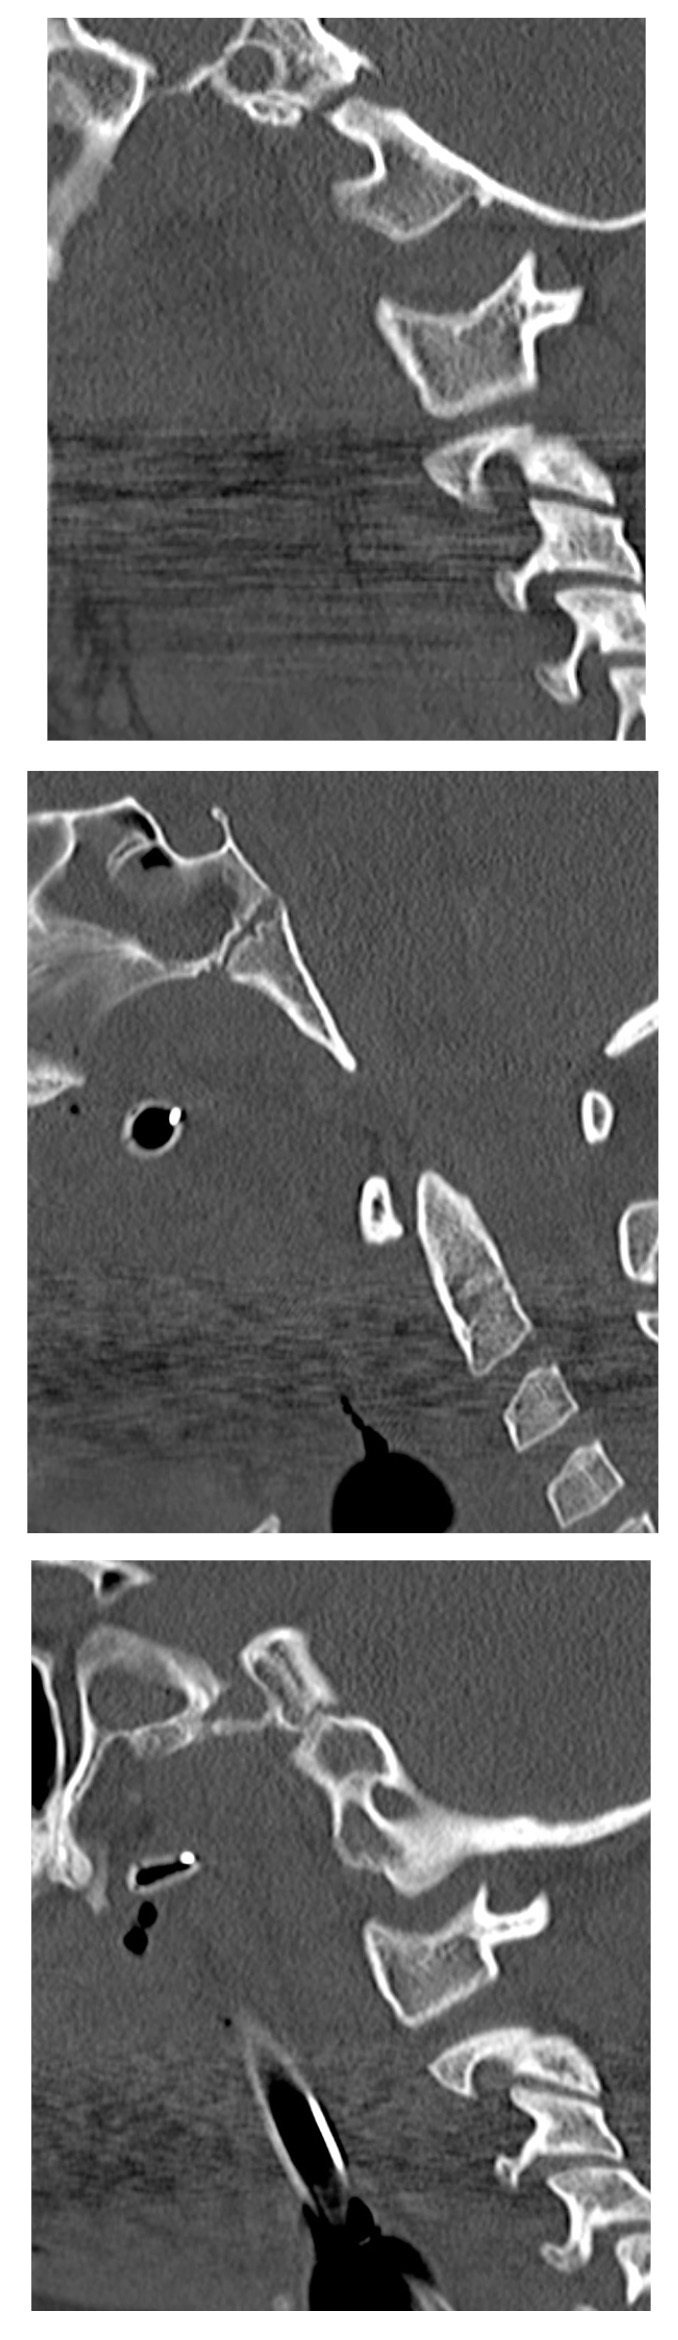

Finally, cervical distraction injuries deserve special consideration. While this type of injury is somewhat rare, it is much more likely in pediatric patients compared to adult patients. Strong clinical suspicion from the mechanism of injury and abnormal interspinous distances on X-ray may lead to diagnosis of distraction injury. These sometimes can be difficult to detect on X-rays alone and may require a CT scan if suspicion is high.30 For an example of this, see Figure 3. Sagittal images from non-contrast CT show craniocervical dissociation injury, with markedly increased distance between the occipital condyles and the lateral masses of C1, and associated hematomas (best seen along the clivus).

Figure 3. Craniocervical Dissociation Injury |

Saggital images from non-contrast computed tomography show craniocervical dissociation injury, with markedly increased distance between the occipital condyles and the lateral masses of C1, and associated hematomas (best seen along the clivus). Source: Courtesy of Mark Warren, DO, Dayton Children’s Hospital, Department of Radiology |